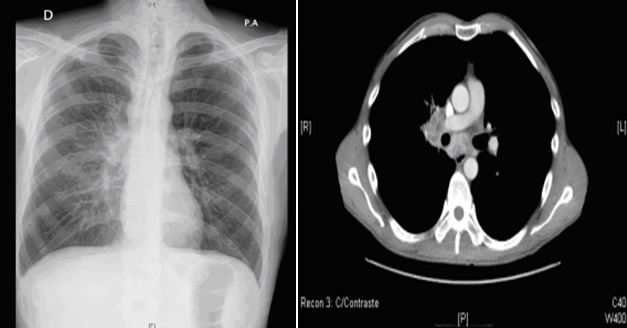

Paciente de 43 años, ExADVP, VIH positivo diagnosticado en 1992, categoría A3. Sin TAR por decisión propia desde el año 2006. Último control realizado en Julio 2010 con CD4 de 10 células/µL que además supone el nadir del paciente, y RNA-VIH de 195.920 cop/ml. Hepatitis crónica VHC genotipo 3 tratada y con respuesta virológica sostenida. Fumador de un paquete al día. Consulta en Septiembre de 2010 por cuadro de 7 días de evolución caracterizado por sensación febril, astenia y tos escasamente productiva que es tratado inicialmente por su médico de cabecera con amoxicilina-clavulánico sin mejoría. En la exploración física destaca un aceptable estado general, temperatura de 38,2o C, hemodinamicamente estable, eupneico, sin adenopatías palpables, algún roncus disperso en la auscultación pulmonar; resto de la exploración sin datos relevantes. En la analítica destaca una linfopenia de 870 cel/µL, Hb de 11,3 g/dl y Na de 134 mEq/L. En la radiografía de tórax se describe un patrón intersticial en hemitórax derecho de predominio en LI y LM (Figura 1). En el TAC toracoabdominal se visualiza un conglomerado adenopático en hilio pulmonar derecho de unos 4 cm con adenopatías confluentes necróticas. También se observan otros ganglios más pequeños a lo largo de la cadena paratraqueal y traqueobronquial derecha y en la región subcarinal, la mayor parte de ellos con necrosis central y realces capsulares. No otras localizaciones.

Extensos cambios enfisematosos. (Figura 2). En el esputo inducido la auramina y el cultivo posterior para micobacterias son negativos y el antígeno de Pn jirovecii también resulta negativo.